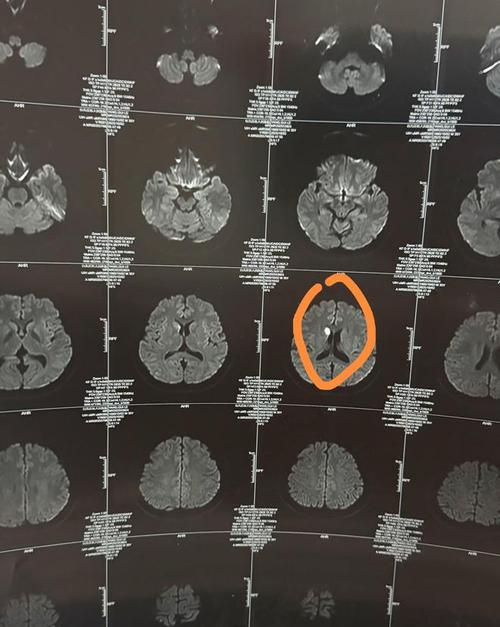

“稍微有点脑梗”在医学上通常指什么?

医生在口头沟通时,为了方便患者理解,可能会用“稍微有点”这样的词,在影像学上,这很可能对应以下几种情况:

- 腔隙性脑梗塞: 这是最常见的情况,它不是我们通常想象的那种大面积、致命性的脑梗,它是因为大脑深处一些非常细小的血管堵塞了,导致一小块脑组织缺血、坏死,这个“小块”非常小,可能只有几毫米,通常不会引起明显的、严重的症状(比如瘫痪、失语等),很多人甚至根本不知道自己有过。

- 无症状性脑梗塞: 梗塞的病灶确实存在,但因为位置不关键或范围太小,没有引发任何可以察觉的临床症状。

医生说“稍微有点”,大概率是指发现了一些陈旧性的、范围很小的、没有引起明显症状的缺血病灶,这更像是一个“健康警报”,提醒您需要关注和管理自己的脑血管健康,而不是一个“疾病判决”。